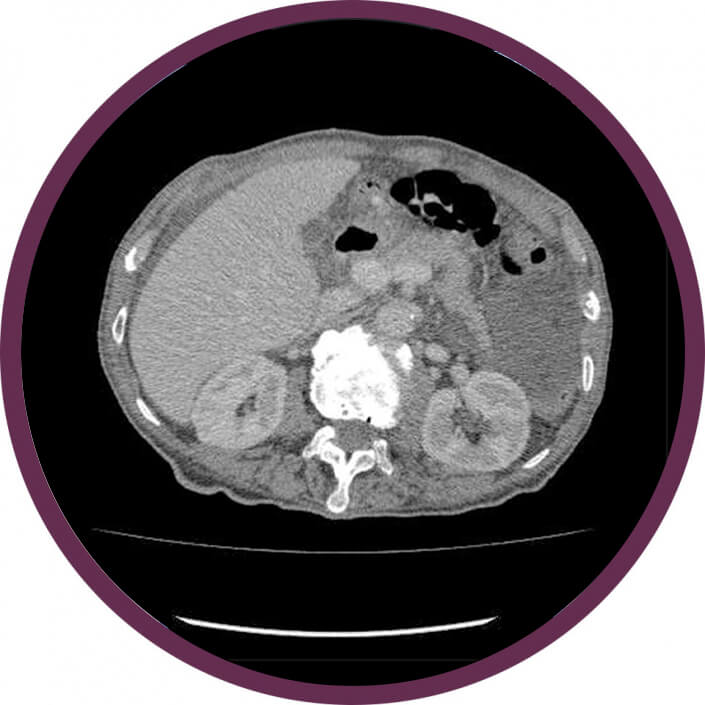

Has – és kismedence CT

Has és kismedence natív és kontrasztos CT

Mi a vizsgálat célja?

A CT vizsgálat alapvető jelentőségű diagnosztikus eljárás a teljes hasüregben lévő (pl.: máj, epeutak, hasnyálmirigy) gyulladásos elváltozásai, illetve daganatos betegségek gyanúja vagy már szövettanilag igazolt daganatos kórképek kiterjedésének és esetleges áttétképződésének kimutatásában. A vizsgálat nagy pontossággal kimutatja az elsődleges (primer) daganatos folyamat kiterjedését, környezethez való viszonyát, a daganat esetleges környező (lokoregionális) nyirokcsomókba terjedését és a távoli áttétek jelenlétét. A CT vizsgálatot alkalmazhatjuk a műtéti kezelés kivitelezhetőségének (operabilitás) megítélésére, valamint a sikeres műtéti és onkológiai (daganatgátló gyógyszeres és sugárkezelés) terápiát követően a betegség teljes gyógyulásának (teljes remisszió), részleges gyógyulásának (részleges remisszió) vagy változásának (progressió) megítélésére és fél vagy évenkénti utánkövetésére.

Milyen előkészület szükséges?

A CT vizsgálat előtt fontos a kezelőorvossal, sebésszel vagy onkológussal történő konzultáció, hisz a CT vizsgálat során, sugárterhelés és kontrasztanyag adása is történik, így a vizsgálatot csak orvosi javaslat alapján végezzük. A vizsgálat előtt 6 órával már nem szabad enni, tiszta vizet azonban a beteg fogyaszthat. A kontrasztanyag adása előtt meg kell vizsgálni a vese működését jelző labor paramétereket, mivel súlyosan károsodott (beszűkült) vesefunkció esetén a kontrasztanyag adása lehetőség szerint elkerülendő. Ismert kontrasztanyag allergia esetén a kontrasztanyag adása tilos (kontraindikált). A kontrasztos vizsgálatok előtt a metformin tartalmú cukorbetegségben adott gyógyszerek szedését be kell szűntetni.